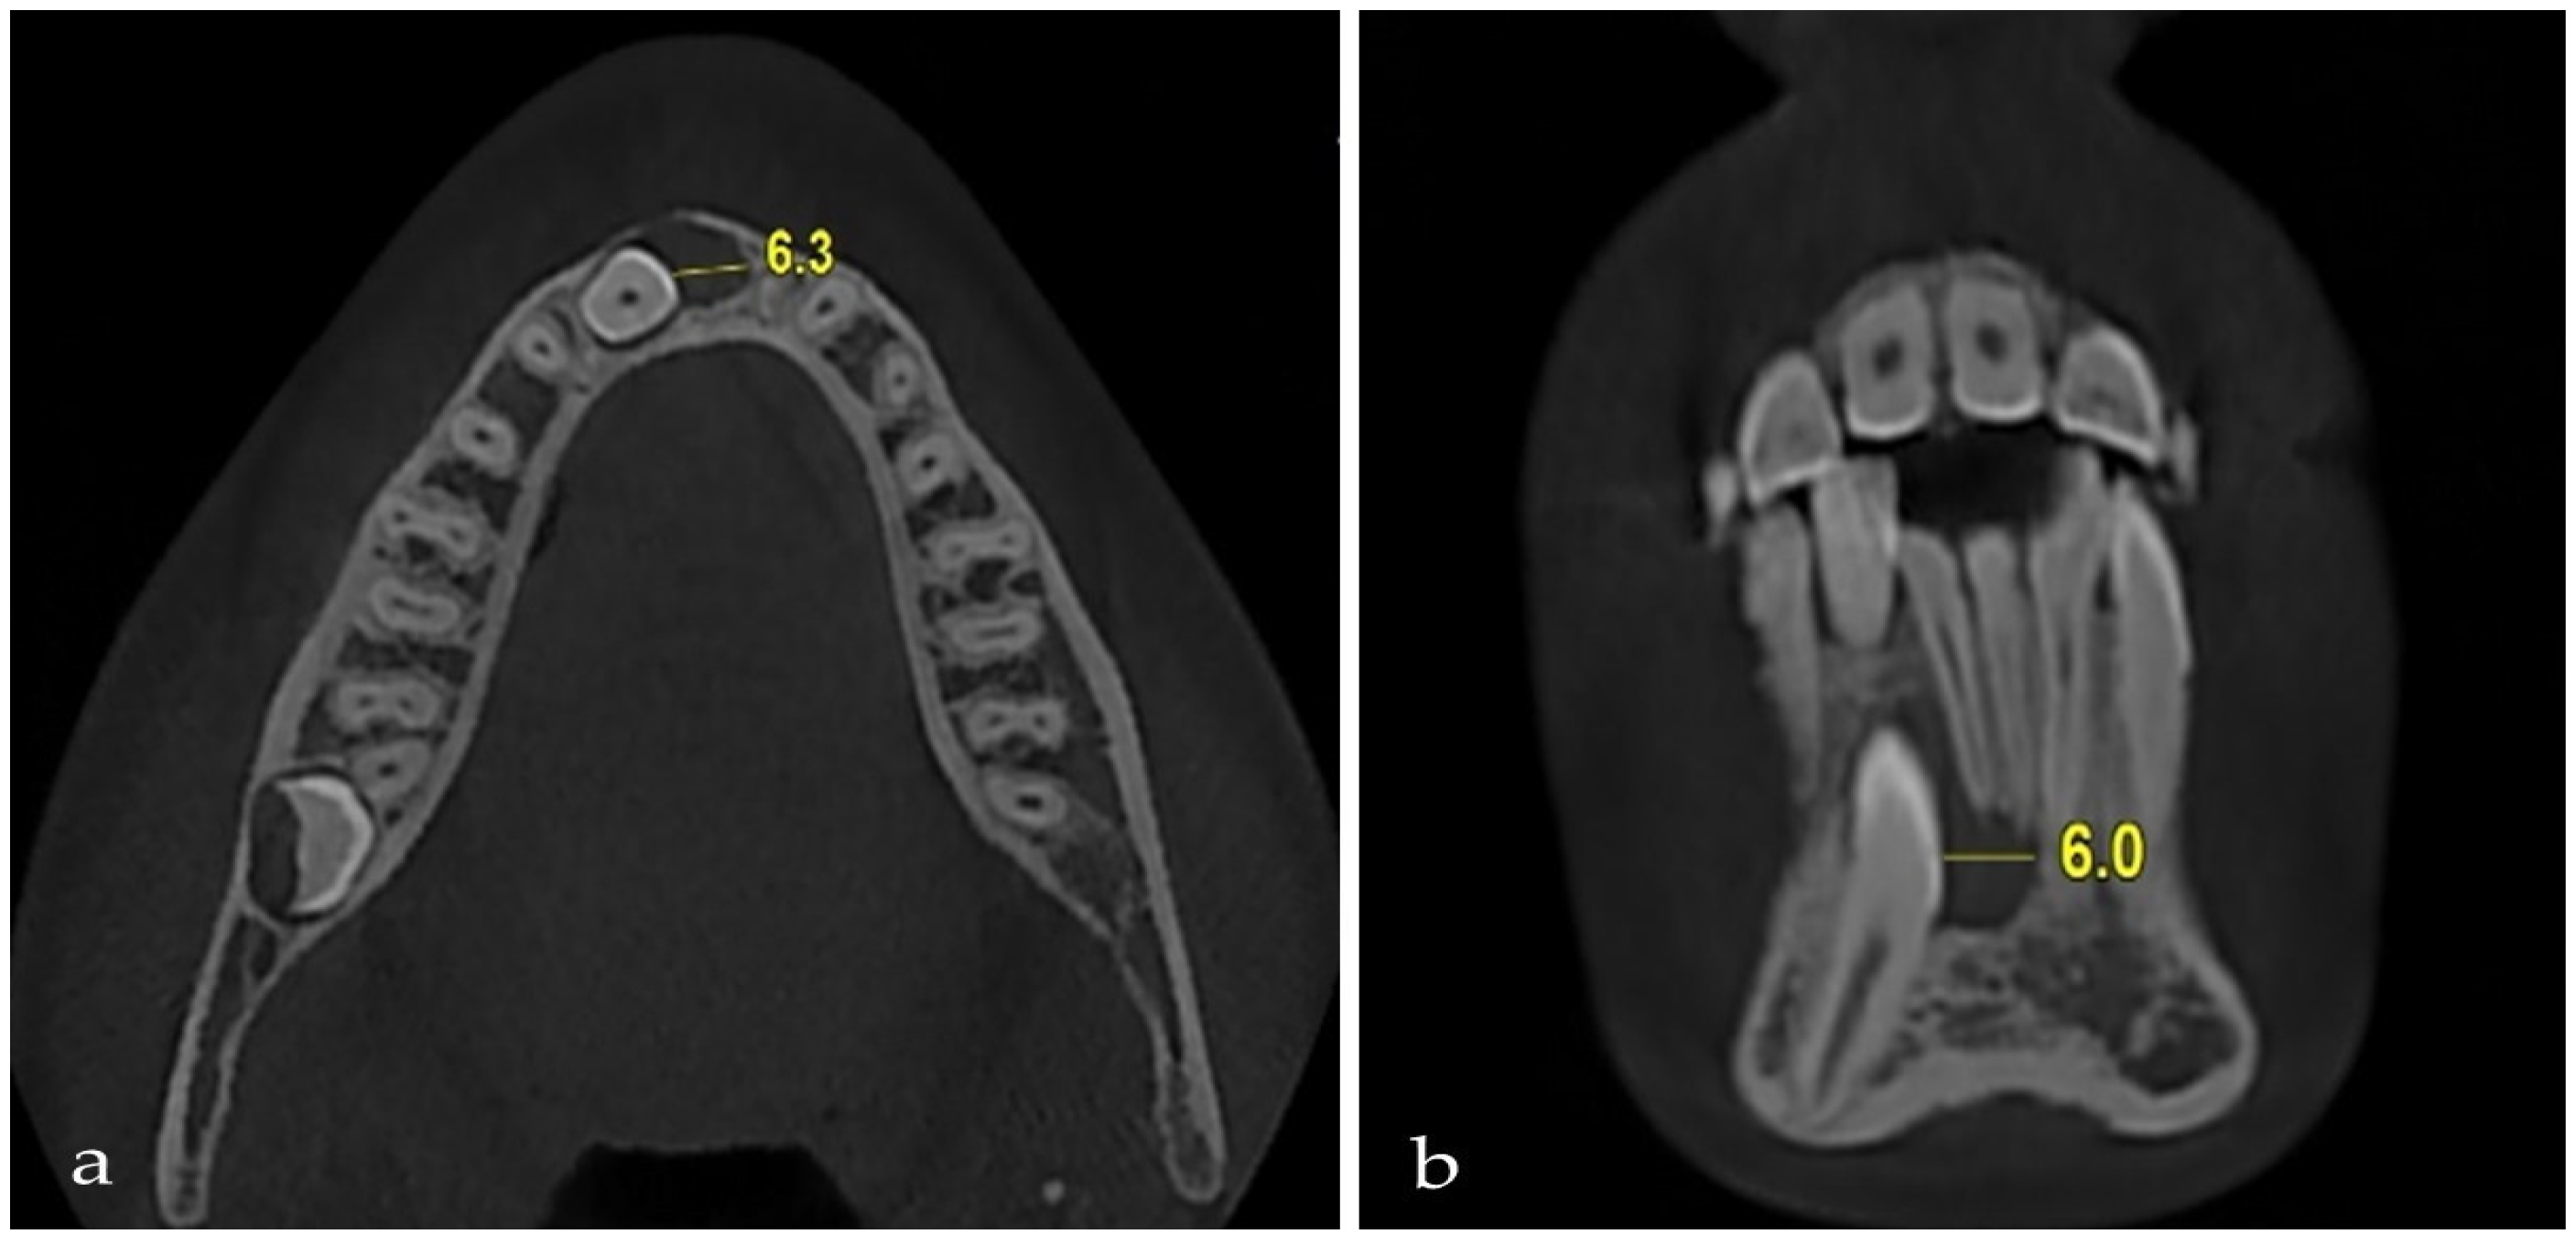

| Impacted Side | Non-Impacted Side | Test Statistic | ||

| Mean ± SD Median (IQR) | Mean ± SD Median (IQR) | z; t | p | |

| Mesiodistal width of the canine | 6.78 ± 0.41 | 6.56 ± 0.40 | t = 2.617 | 0.010 |

| 6.70 (0.50) | 6.60 (0.50) | |||

| Interpremolar width | 15.69 ± 2.29 | 16.45 ± 1.42 | z = 1.864 | 0.062 |

| 16.00 (2.78) | 16.80 (1.65) | |||

| Intermolar width | 21.86 ± 2.27 | 22.44 ± 2.06 | t = 1.393 | 0.166 |

| 22.15 (2.90) | 22.35 (2.80) | |||

| Arch length | 29.92 ± 2.38 | 32.21 ± 2.18 | t = 5.194 | <0.001 |

| 30.05 (2.80) | 32.40 (3.00) | |||